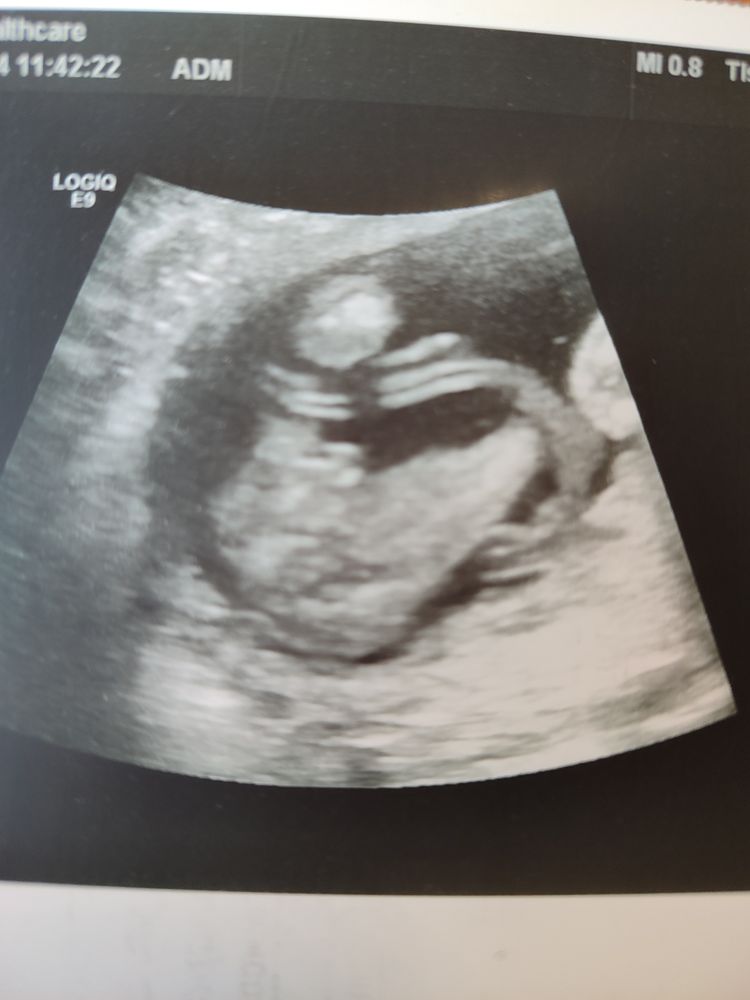

Пол малыша, 16 недель

Предполагаю что мальчик, поздравляю вас)

По моему там мужские причендалики))

Мне в 17 недель сказали) Бывшей подруге тоже в 17 недель сказали пол. Девочку спрогнозировали. Она не поверила, потому что чувствовала, что это мальчик. Следующее УЗИ показало мальчика.

Да, мальчишка💙

Пол ребенка, первый скрининг Второй скрининг! Экватор, смех сквозь слезы.